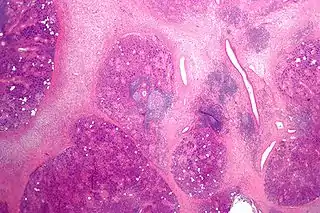

![]() Micrografía de una sialadenitis crónica | ||